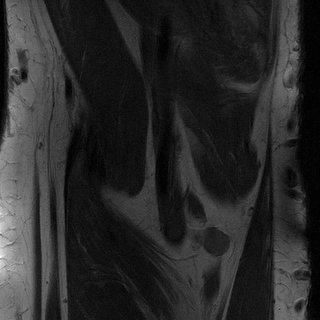

Reconstructing magnetic resonance (MR) images from undersampled data is a challenging problem due to various artifacts introduced by the under-sampling operation. Recent deep learning-based methods for MR image reconstruction usually leverage a generic auto-encoder architecture which captures low-level features at the initial layers and high?level features at the deeper layers. Such networks focus much on global features which may not be optimal to reconstruct the fully-sampled image. In this paper, we propose an Over-and-Under Complete Convolu?tional Recurrent Neural Network (OUCR), which consists of an overcomplete and an undercomplete Convolutional Recurrent Neural Network(CRNN). The overcomplete branch gives special attention in learning local structures by restraining the receptive field of the network. Combining it with the undercomplete branch leads to a network which focuses more on low-level features without losing out on the global structures. Extensive experiments on two datasets demonstrate that the proposed method achieves significant improvements over the compressed sensing and popular deep learning-based methods with less number of trainable parameters. Our code is available at https://github.com/guopengf/OUCR.